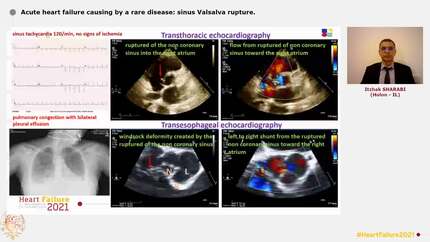

Acute heart failure causing by a rare disease: sinus Valsalva rupture.